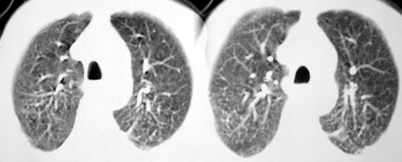

以下是引用sdqzwyx在2005-11-7 19:59:00的发言:[br]双肺弥漫大小不等的粟粒状结节影;肺纹理走行失去自然,粗细不均,边缘不规则,小叶间隔增厚;左上肺示不规则形致密影,从斑块边缘向周围伸出长短不一的致密索条影,临近的血管、支气管和叶间胸膜等结构受牵拉移位;左下肺示不规则团块状影,其内示空洞,洞内壁尚光整,左侧胸腔积液。右肺下叶背段亦示部分病灶融合。双肺可见局限性肺气肿。[br]诊断:结合病史符合三期矽肺表现(少数矽肺纤维斑块内可以形成空洞,一般认为是斑块中央感染引起坏死所致)但尘肺病人易合并肺结核,诊断可为三期+tb。所以此病人应进一步检查是否合并结核。